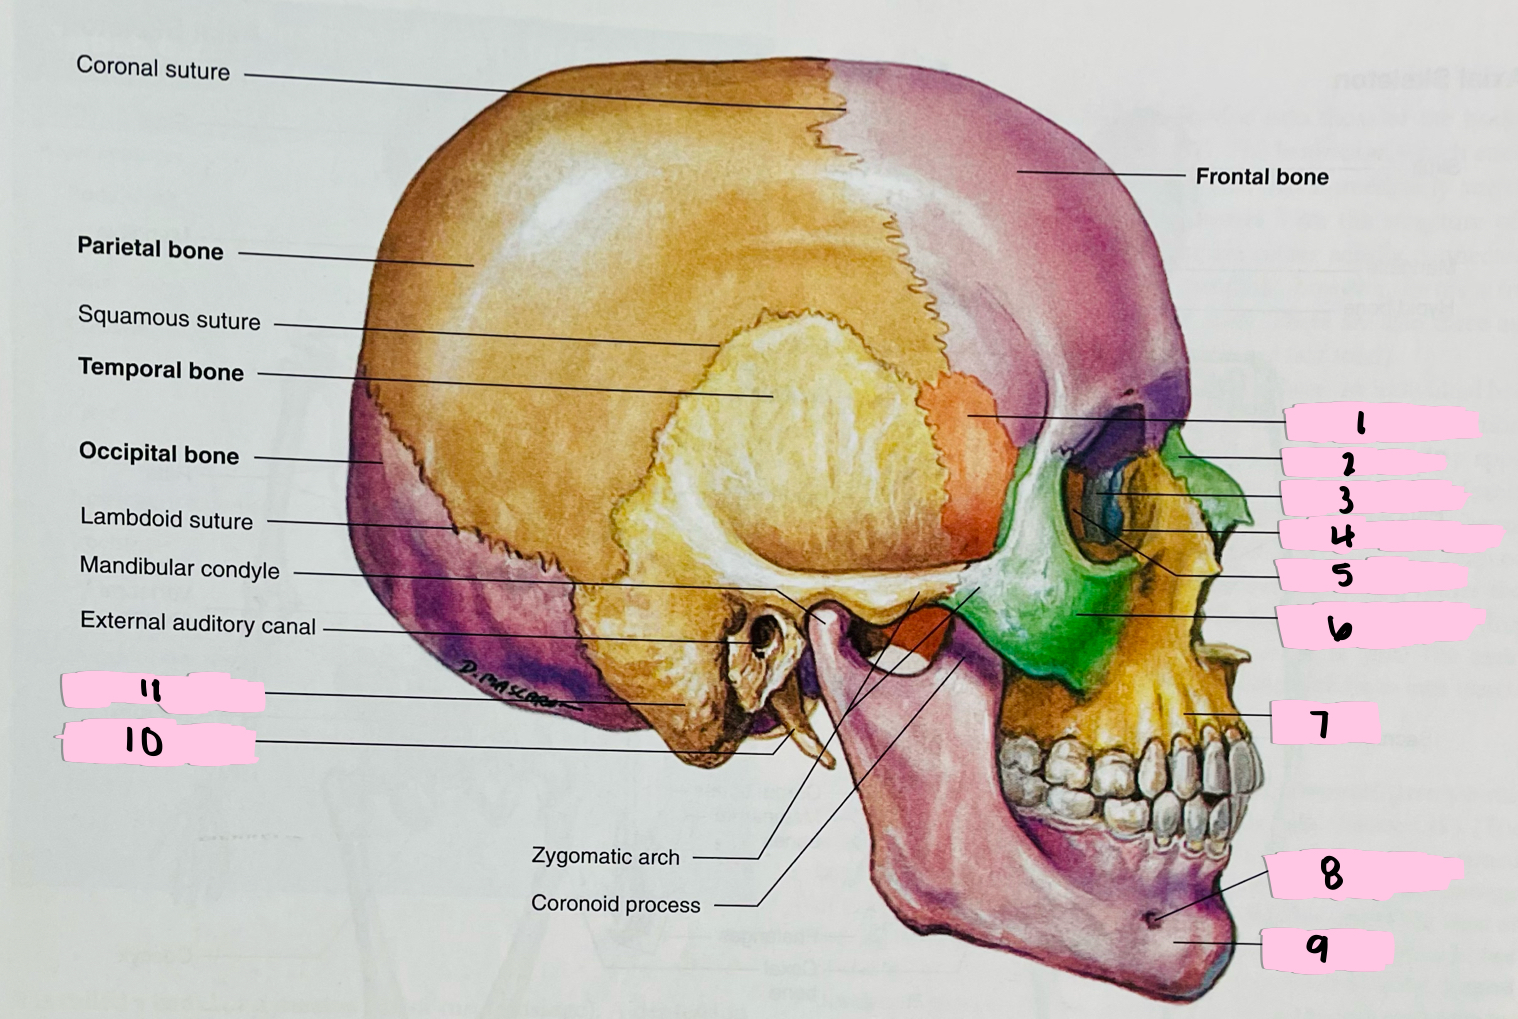

What is 1 pointing to?

Sphenoid bone

What is 2 pointing to?

Nasal bone

What is 3 pointing to?

Lacrimal bone

What is 4 pointing to?

Nasolacrimal canal

What is 5 pointing to?

Ethmoid bone

What is 6 pointing to?

Zygomatic bone

What is 7 pointing to?

Maxilla

What is 8 pointing to?

Mental foramen

What is 9 pointing to?

Mandible

What is 10 pointing to?

Styloid process

What is 11 pointing to?

Mastoid process